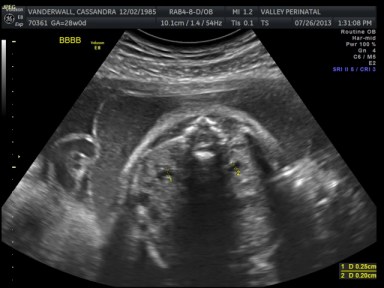

The weight of each baby is estimated based on the length of the baby’s humerus (bone in upper arm) and femur (bone in upper leg), the circumference of their abdomen and their head circumference.

The biggest one in the bunch is Baby B at 2lbs and 12oz at the 62nd percentile. Little Elle Rose (Baby E) is the munchkin, but not by much as baby D and Theo (baby A) are also the same weight (2 ½ lbs) but just a bit longer. At this rate, when the baby’s are measured again at 32 weeks they will be about 1lb heavier each. Let’s just hope this Mama can keep up!

All of their organs (kidneys, bladders, hearts, brains, stomachs) look great and are also appropriate sizes. The blood flow to Elle has improved and has stabilized. All heart rates remain within normal limits, and are often on the higher side, which is probably because they just can’t sit still. We are truly excited to meet our little wiggle worms!